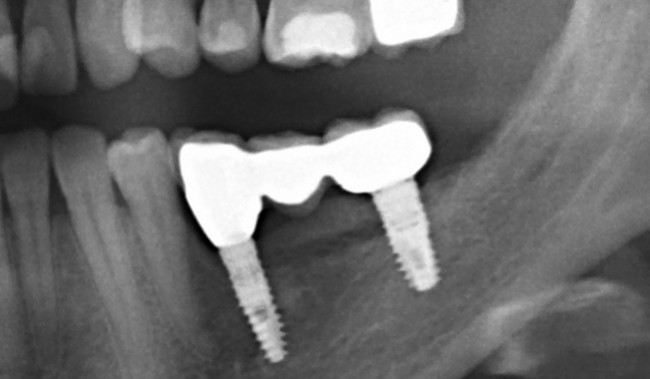

Остеопластические операции: факторы успеха